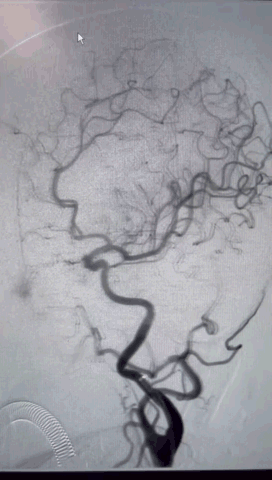

术前影像学检查结果

右侧股动脉穿刺,置8F鞘管,泥鳅导丝携6F 90cm Locaste输送导管内衬125cm多功能单弯导管超选至左侧颈内动脉C1段,6F 115cm Skathi远端通路导管到达C4段。

依据动脉瘤3D,调整机架位置使得动脉瘤及载瘤动脉显影最佳,Echelon-10微导管塑形理想,顺利超选至瘤内,先尝试单纯弹簧圈栓塞,必要时再采用支架辅助。